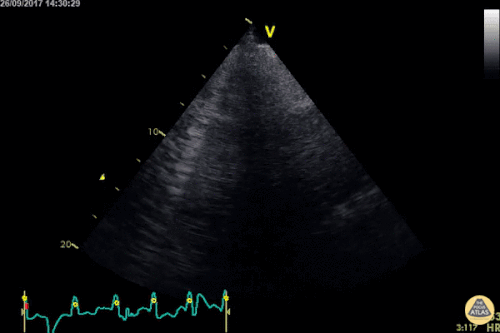

Question 2: This 65-year-old woman presents with dyspnea and fever. She presented to her doctor a week ago with fever and cough, for which she was treated with azithromycin. She was feeling better for a while, but has been declining for the past couple days.

- Describe the ultrasonographic findings.

- What is your differential diagnosis for this ultrasound pattern?

- What is your diagnostic and therapeutic plan for this patient?